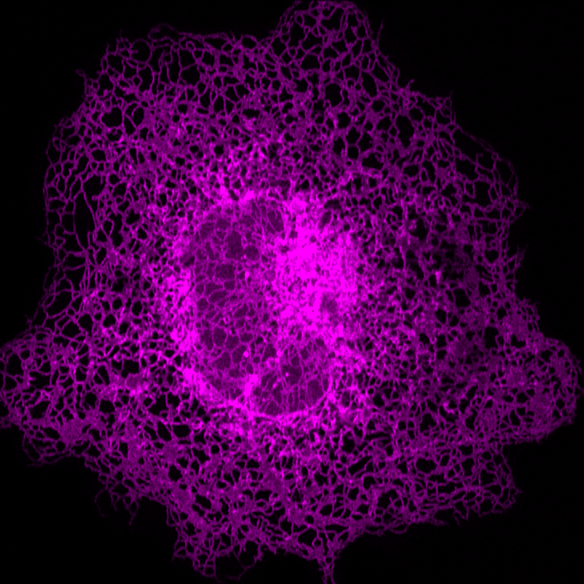

先进光学显微成像显现单个细胞内部的内质网

因为内质网是细胞中十分复杂且巨大的动态网络,其形状和散布非常复杂。据了解,现在科学界没有很好的办法完成准确定量分析内质网的拓扑结构和运动状况。剑桥无限极研讨中心研讨人员经过3年的技能攻关,总算在此范畴获得了突破性发展,将人工智能和超高分辨率成像系统结合树立了一套全新的智能分析系统“ERnet”,榜初次完成了对活细胞内质网结构的准确定量分析。凭仗在技能和科学知道上的明显立异性,该效果宣布在全球科学顶刊、生化研讨办法范畴排名榜首的威望刊物《Nature Methods》(IF47.99)。